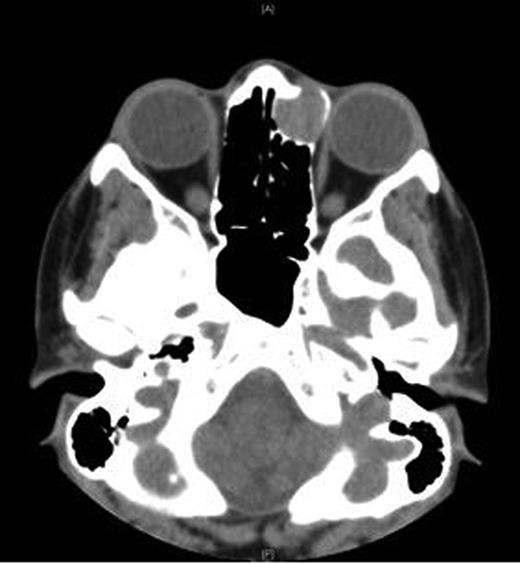

A CT scan of the paranasal sinuses and orbits revealed the cystic expansile 1.6 cm mass at the left medial canthus to be of soft tissue density. The lateral wall of the mass expanded outwards into the orbit (suggesting an anterior ethmoidal mucocele) rather than being pushed medially (which could have been indicative of a dacryocystocele) (Fig. 4).